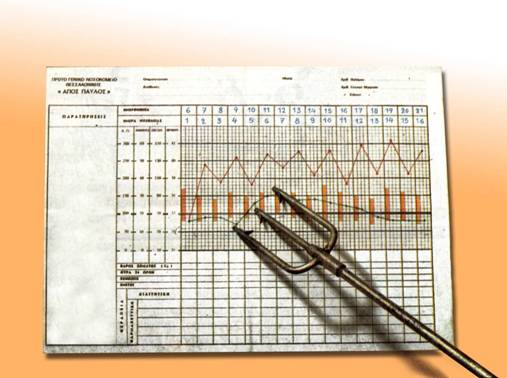

Η προηγούμενη αφήγηση οργανώνεται όπως είναι φυσικό, πάνω στον άξονα του χρόνου παρουσιάζοντας τη διαδοχή των γεγονότων και τη χρονική τους σχέση (σύγχρονο, προτερόχρονο, υστερόχρονο)*. Παρατηρήστε στο παρακάτω σχεδιάγραμμα πώς η οργάνωση της αφήγησης γύρω από τον άξονα του χρόνου εξυπηρετεί τη συνοχή του κειμένου, και συμπληρώστε το διάγραμμα.

|

Θέμα – κεντρικό γεγονός κατά παράγραφο |

Οργάνωση της αφήγησης γύρω από τον άξονα του χρόνου |

Χρονική σχέση των γεγονότων |

1η παράγραφος Ο τραυματισμός της 9χρονης μικρούλας Α. Μ. στην αμμουδιά σε παραθαλάσσιο θέρετρο. |

σύγχρονο (συνέχισε) |

2η παράγραφος Μεταφορά του παιδιού σε νοσοκομείο της Θεσσαλονίκης και παραπομπή στο χειρουργείο. |

3η παράγραφος Λεπτομέρειες από την εγχείρηση. Η αφαίρεση της τρίαινας. |

4η παράγραφος Κατάληξη επεισοδίου |